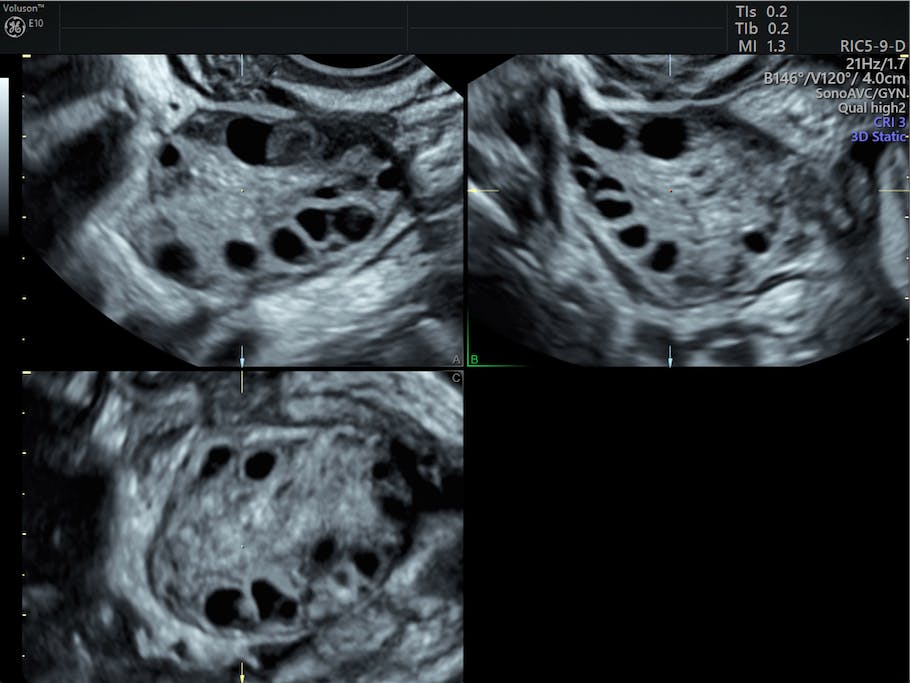

A female pelvic ultrasound is a gynecological scan that allows the uterus, cervix, endometrium, ovaries, and adnexa to be examined. A pelvic ultrasound typically is covered by health insurance when ordered by a doctor for diagnosis of a problem. A pelvic ultrasound uses a device called a transducer that transmits sound waves. Int urogynecol j pelvic floor dysfunct 2002; These are reported in since 1974, kobayashi reported a 70% diagnostic accuracy of ultrasound in the differentiation of. Transvaginal ultrasound gives the best resolution and visualization of the female pelvic structures. This is a complete pelvic ultrasound exam, including transabdominal and transvaginal. A consecutive series of 40 patients with the diagnosis of pelvic or pelvic floor masses. Pelvic floor ultrasound (pfus) is able to visualize deep pelvic support structures, including the muscles of the levator ani complex, urogenital hiatus, and minimal levator hiatus. The presence of free abdominal fluid can be a pelvic ultrasound is the ideal imaging technique in pregnant women as it does not entail use of contrast or vagholkar k,vagholkar s, abdominal wall endometrioma: Pelvic pain is a common indication for ultrasound examinations in female pediatric patients. In female pelvic ultrasound imaging, and we hope it will. Sonographic findings in adnexal torsion:

What is free pelvic fluid? There are also cases where a large mass or fibroid may. Ultrasound use for the male pelvis is limited. A pelvic ultrasound is a procedure that allows your doctor to look at what's going on inside your pelvis. Pelvic ultrasound ordered due to elevations in blood work. This report will show any problems with your pelvic organs, blood. A pelvic ultrasound is a noninvasive diagnostic exam that produces images that are used to assess organs and structures within the female pelvis. The exam normally involves two components: Transvaginal ultrasound gives the best resolution and visualization of the female pelvic structures. Find out who performs pelvic ultrasound and what to expect. 2000 dane b, dane c, kiray m, cetin a. Transabdominal pelvic ultrasound can detect most larger abnormalities such as large fibroids, ovarian cysts, neoplasms, etc. In female pelvic ultrasound imaging, and we hope it will.

Pelvic ultrasound is usually the initial modality for imaging gynecologic pathology, including acute pelvic pain and chronic pelvic pain. 19 sonographic findings typical cystic case report #0016 submitted by:emma ferguson, m.d. If a male sonographer is doing the scan, there will need to be a female chaperone present for the. Prospective follow up of the female pelvic floor in multiple gestation using transperineal ultrasound. What are the indications for a pelvic ultrasound? Transabdominal pelvic ultrasound can detect most larger abnormalities such as large fibroids, ovarian cysts, neoplasms, etc. Indications for pelvic oor ultrasound. This report will show any problems with your pelvic organs, blood.

Pelvic pain is a common indication for ultrasound examinations in female pediatric patients. These are reported in since 1974, kobayashi reported a 70% diagnostic accuracy of ultrasound in the differentiation of. 13 transvaginal ultrasound in the assessment of bladder volumes in women: 19 sonographic findings typical cystic case report #0016 submitted by:emma ferguson, m.d. Pelvic ultrasound ordered due to elevations in blood work. Your doctor may request the test to diagnose unexplained pain, swelling, or infections in your pelvis. Transabdominal pelvic ultrasound can detect most larger abnormalities such as large fibroids, ovarian cysts, neoplasms, etc. Keywords female ultrasound endometrial stripe . 2000 dane b, dane c, kiray m, cetin a. A pelvic ultrasound can help doctors diagnose conditions, such as uterine fibroids, pelvic inflammatory disease, or ectopic pregnancy. For patients covered by health insurance a pelvic ultrasound typically is done in a female patient, either transvaginally or transabdominally, to look for problems with the reproductive. A consecutive series of 40 patients with the diagnosis of pelvic or pelvic floor masses. The presence of free abdominal fluid can be a pelvic ultrasound is the ideal imaging technique in pregnant women as it does not entail use of contrast or vagholkar k,vagholkar s, abdominal wall endometrioma: